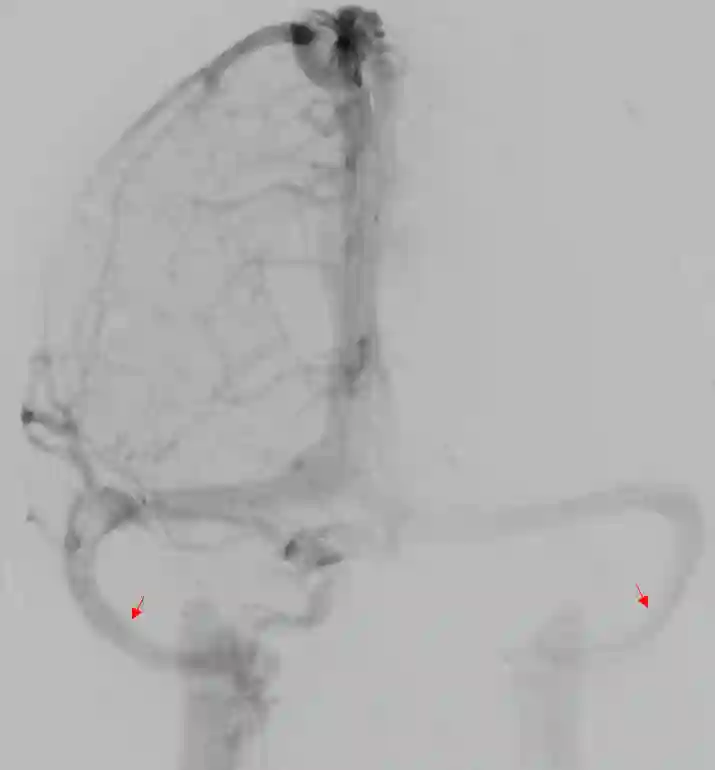

Sinus sigmoideus DSA

Darstellung des Sinus sigmoideus auf beiden Seiten in einer venösen Phase einer digitalen Subtraktionsangiographie.